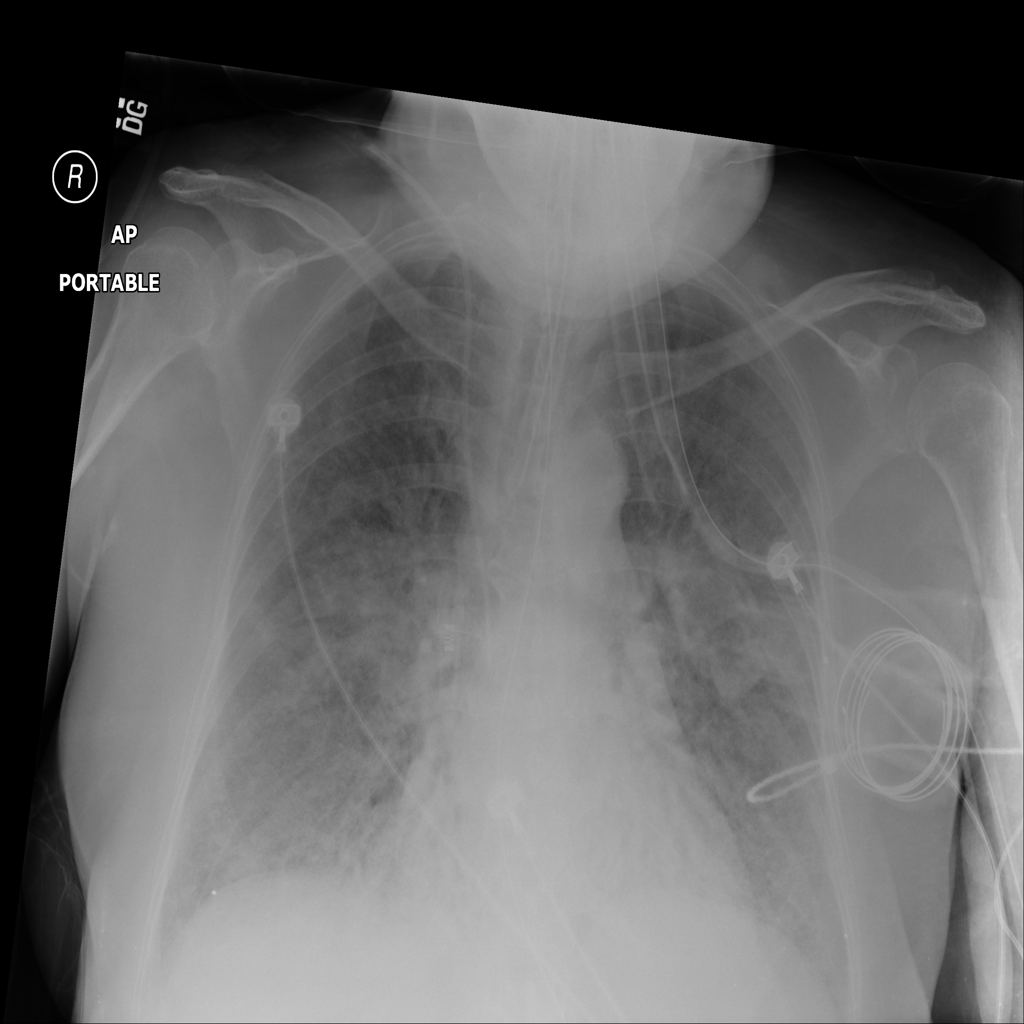

Consolidation

Consolidation refers to air-space filling that makes part of the lung appear denser on imaging.

Showing up to 90 reference images for Consolidation.

PAT-B733 · IMG-000Consolidation

PAT-B733 · IMG-000

PA